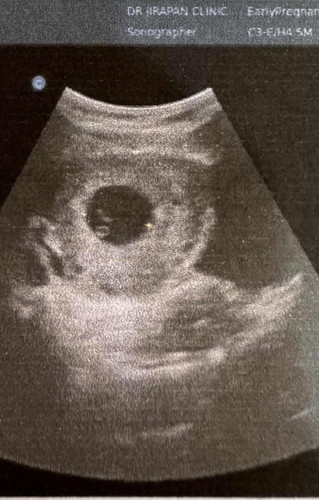

ของลูกคนแรกค่ะ (ทำiui) ในภาพน้องได้ 7w1d ขนาดตัววันได้ 2.6 cm ฟังเสียงหัวใจได้ชัดค่ะ จากนั้นอีกคนเมื่อปีที่แล้ว (iui) มาซาวด์ฟังเสียงตอน 7 วีค ก็ได้ยินค่ะ แต่อ่อนมากๆเลย หมอนัดมาฟังอีกทีตอน 9w ก็ได้ยินเสียงดีขึ้น แต่สีหน้าคุณหมอก็บ่งบอกให้รู้ได้ว่า น่าจะมีปัญหาอะไรบางอย่าง สุดท้าย น้องฝ่อไป กว่าจะรู้อีกทีก็มีเลือดออกนิดๆ ในวีคที่ 12 กำลังจะไปตรวจนิฟตี้พอดี สรุปคือน้องไม่เจริญเติบโตต่อ มาปีนี้สู้อีกรอบ (ทำicsi) 5Wวันนี้ค่ะ รออีก 2 วีค จะไปฟังเสียงหัวใจ แอบตื่นเต้นมากๆค่ะ และขอให้คุณแม่อย่ากังวลค่ะ และขอให้น้องแข็งแรง ได้ยินเสียงหัวใจดังๆเลยค่ะ ❤️